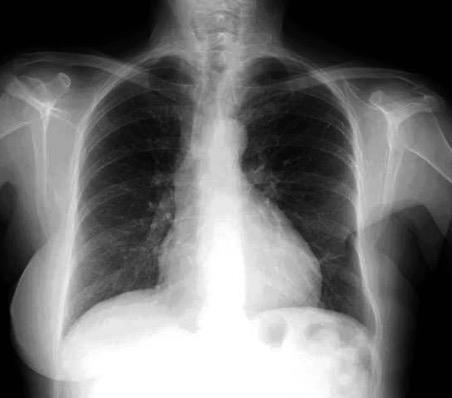

Carcinoma de mama izquierda

Nódulo en língula.

Cirugía de Ca .de mama hace 23 añosedema de brazo y ganglio en axila. ¡Metástasis!.